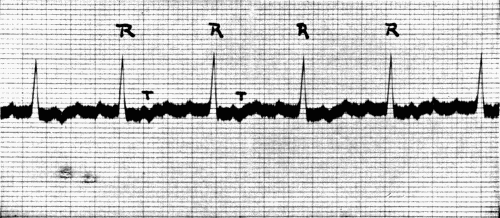

39. Normal electrocardiogram128

40. Auricular flutter132

41. Auricular fibrillation134

[22]

42. Auricular fibrillation134